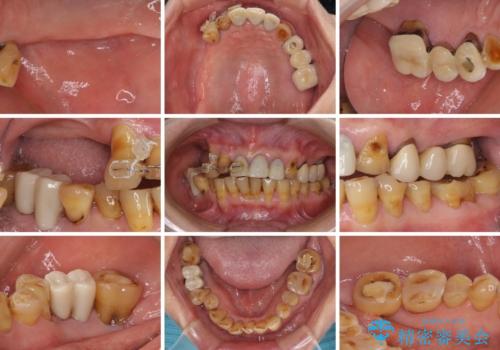

治療途中で放置してしまった前歯 オールセラミッククラウンによる補綴治療

- 前歯の部分矯正や仮歯に置き換えるなど、治療途中のまま放置してしまったとのことで来院された患者様です。

骨格的に下顎骨が前方にあり、歯列の幅も下顎の方が大きいため、奥歯に負担のかかりやすい咬合でした。

大臼歯部は、上下左右ともに咬合により問題が生じており、骨格的な問題から積極的な治療をするべきか判断の難しい状況でした。

臼歯部は痛みが生じている歯に絞って処置を行い、それ以外については手を加えず、現状維持を心がけることとしました。

前歯部については抜歯が必要な歯を抜歯し、インプラントやブリッジなどにより補綴治療を行うこととしました。